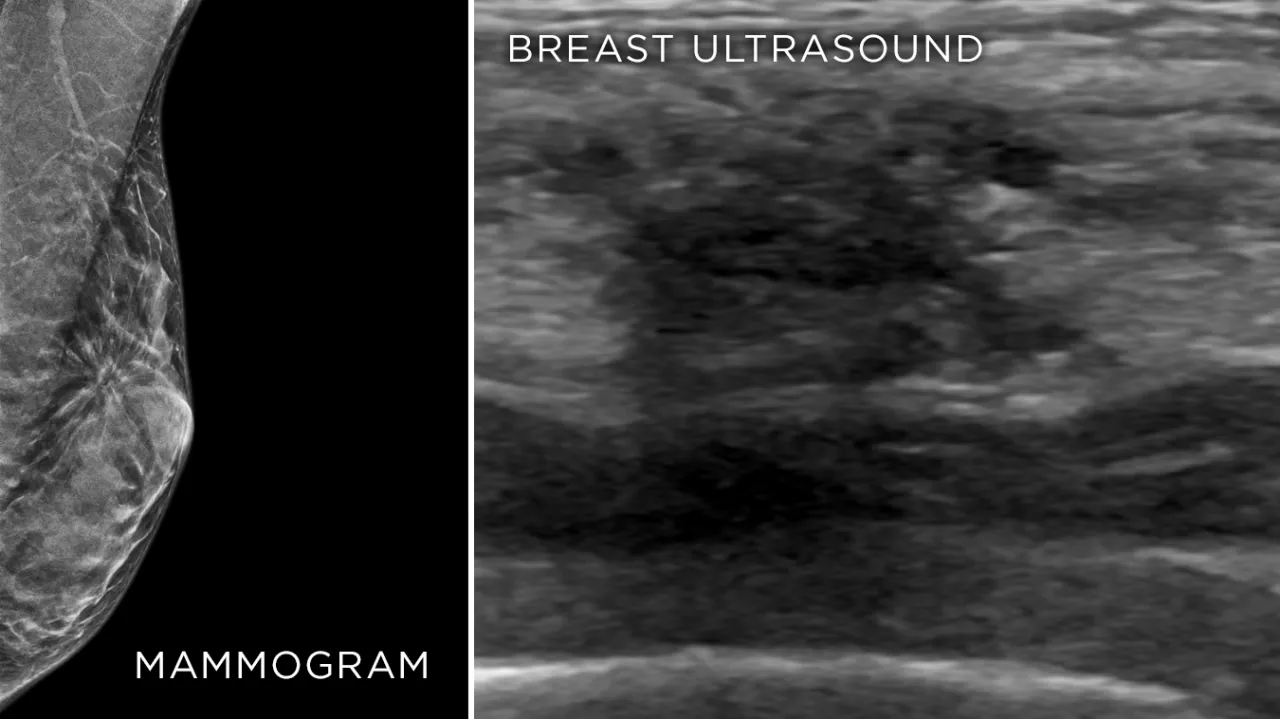

Radiolog to specjalista, który odgrywa kluczową rolę w procesie diagnostycznym. To właśnie on wykonuje i interpretuje badania obrazowe piersi, takie jak USG piersi i mammografia. Kiedy Twój ginekolog lub onkolog wystawi skierowanie na jedno z tych badań, to właśnie do radiologa trafisz.

Zadaniem radiologa jest nie tylko techniczne wykonanie badania, ale przede wszystkim dokładna analiza uzyskanych obrazów i sporządzenie precyzyjnego opisu. To na podstawie jego oceny lekarz kierujący będzie mógł podjąć decyzję o dalszych krokach. Warto pamiętać, że doświadczenie radiologa ma ogromne znaczenie dla trafności diagnozy, dlatego zawsze polecam wybierać sprawdzone placówki z dobrymi specjalistami.

Wybór odpowiedniego badania obrazowego piersi zależy przede wszystkim od wieku kobiety i struktury tkanki piersiowej. Zarówno USG, jak i mammografia, są niezwykle ważne, ale mają różne zastosowania i skuteczność w różnych grupach wiekowych.

USG piersi to podstawowe badanie profilaktyczne, które ja, jako Wojciech Malinowski, zawsze zalecam, zwłaszcza kobietom poniżej 40.-50. roku życia. Wynika to z faktu, że w tym wieku piersi mają zazwyczaj gęstą, gruczołową budowę, co sprawia, że mammografia jest mniej skuteczna w wykrywaniu zmian. Ultradźwięki doskonale radzą sobie z obrazowaniem takiej tkanki, pozwalając na precyzyjną ocenę.

Mammografia: Złoty standard po 40. roku życia

Mammografia jest uznawana za "złoty standard" w diagnostyce raka piersi u kobiet po 40.-50. roku życia. W tym wieku tkanka piersi staje się bardziej tłuszczowa, co sprawia, że mammografia, wykorzystująca promieniowanie rentgenowskie, jest znacznie skuteczniejsza w wykrywaniu drobnych zwapnień i wczesnych zmian nowotworowych, które mogą być niewidoczne w USG. Różnica polega na tym, że USG lepiej obrazuje zmiany w gęstej tkance, natomiast mammografia jest niezastąpiona w piersiach z przewagą tkanki tłuszczowej.